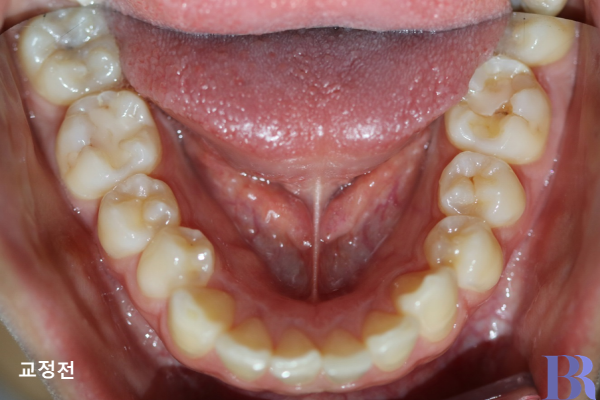

발치교정 : 하악 교정전 모습

편측교정 케이스 : 아래 치아 모습,

아랫니는 발치 없이 교정을 마무리함.

아래치아 모습입니다.

아랫니는 발치없이 교정이

마무리된 것을 알 수 있습니다.